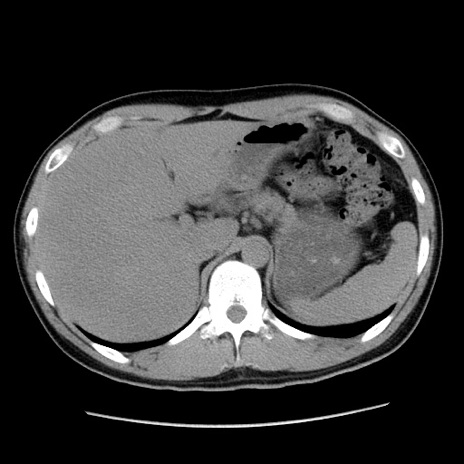

症例36(横断像)

【症例】20歳代 男性

【主訴】心窩部痛

【現病歴】今朝より上腹部痛あり。一旦軽快していたが再度出現したため救急要請。昨日夕に白身の魚を含む刺身を食べた。

【身体所見】BP 136/89mmHg、HR 74/min、BT 37.0℃、腹部:膨満、軟、心窩部に圧痛あり。反跳痛なし、筋性防御なし、腸雑音やや亢進あり。

【データ】WBC 17700、CRP 0.48